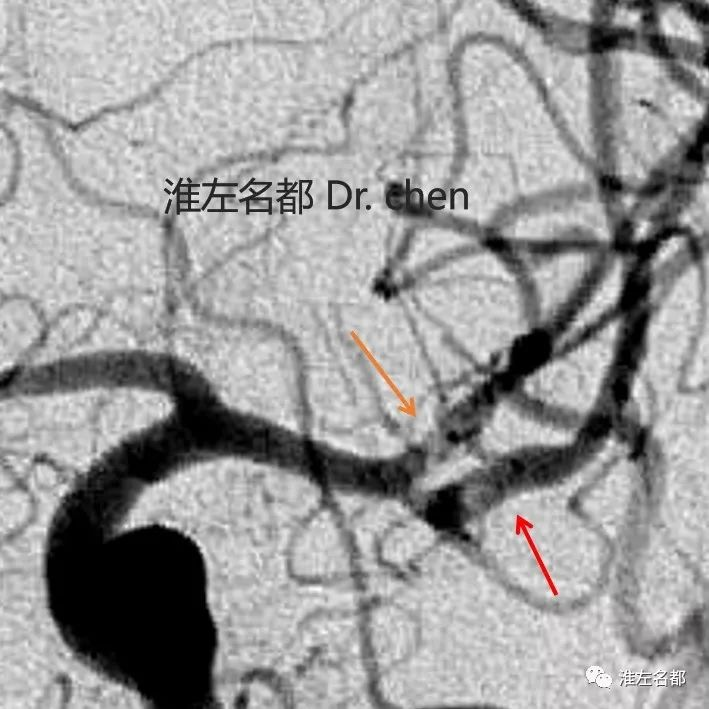

△左侧颈动脉DSA(正位):左侧大脑中动脉上干

(橙箭)、下干(红箭)近端局部管腔扩张,

造影剂显影较淡(提示局部管腔不规则狭窄)。

△左侧颈动脉DSA(右前斜位):

左侧大脑中动脉下干近端狭窄(红箭)。